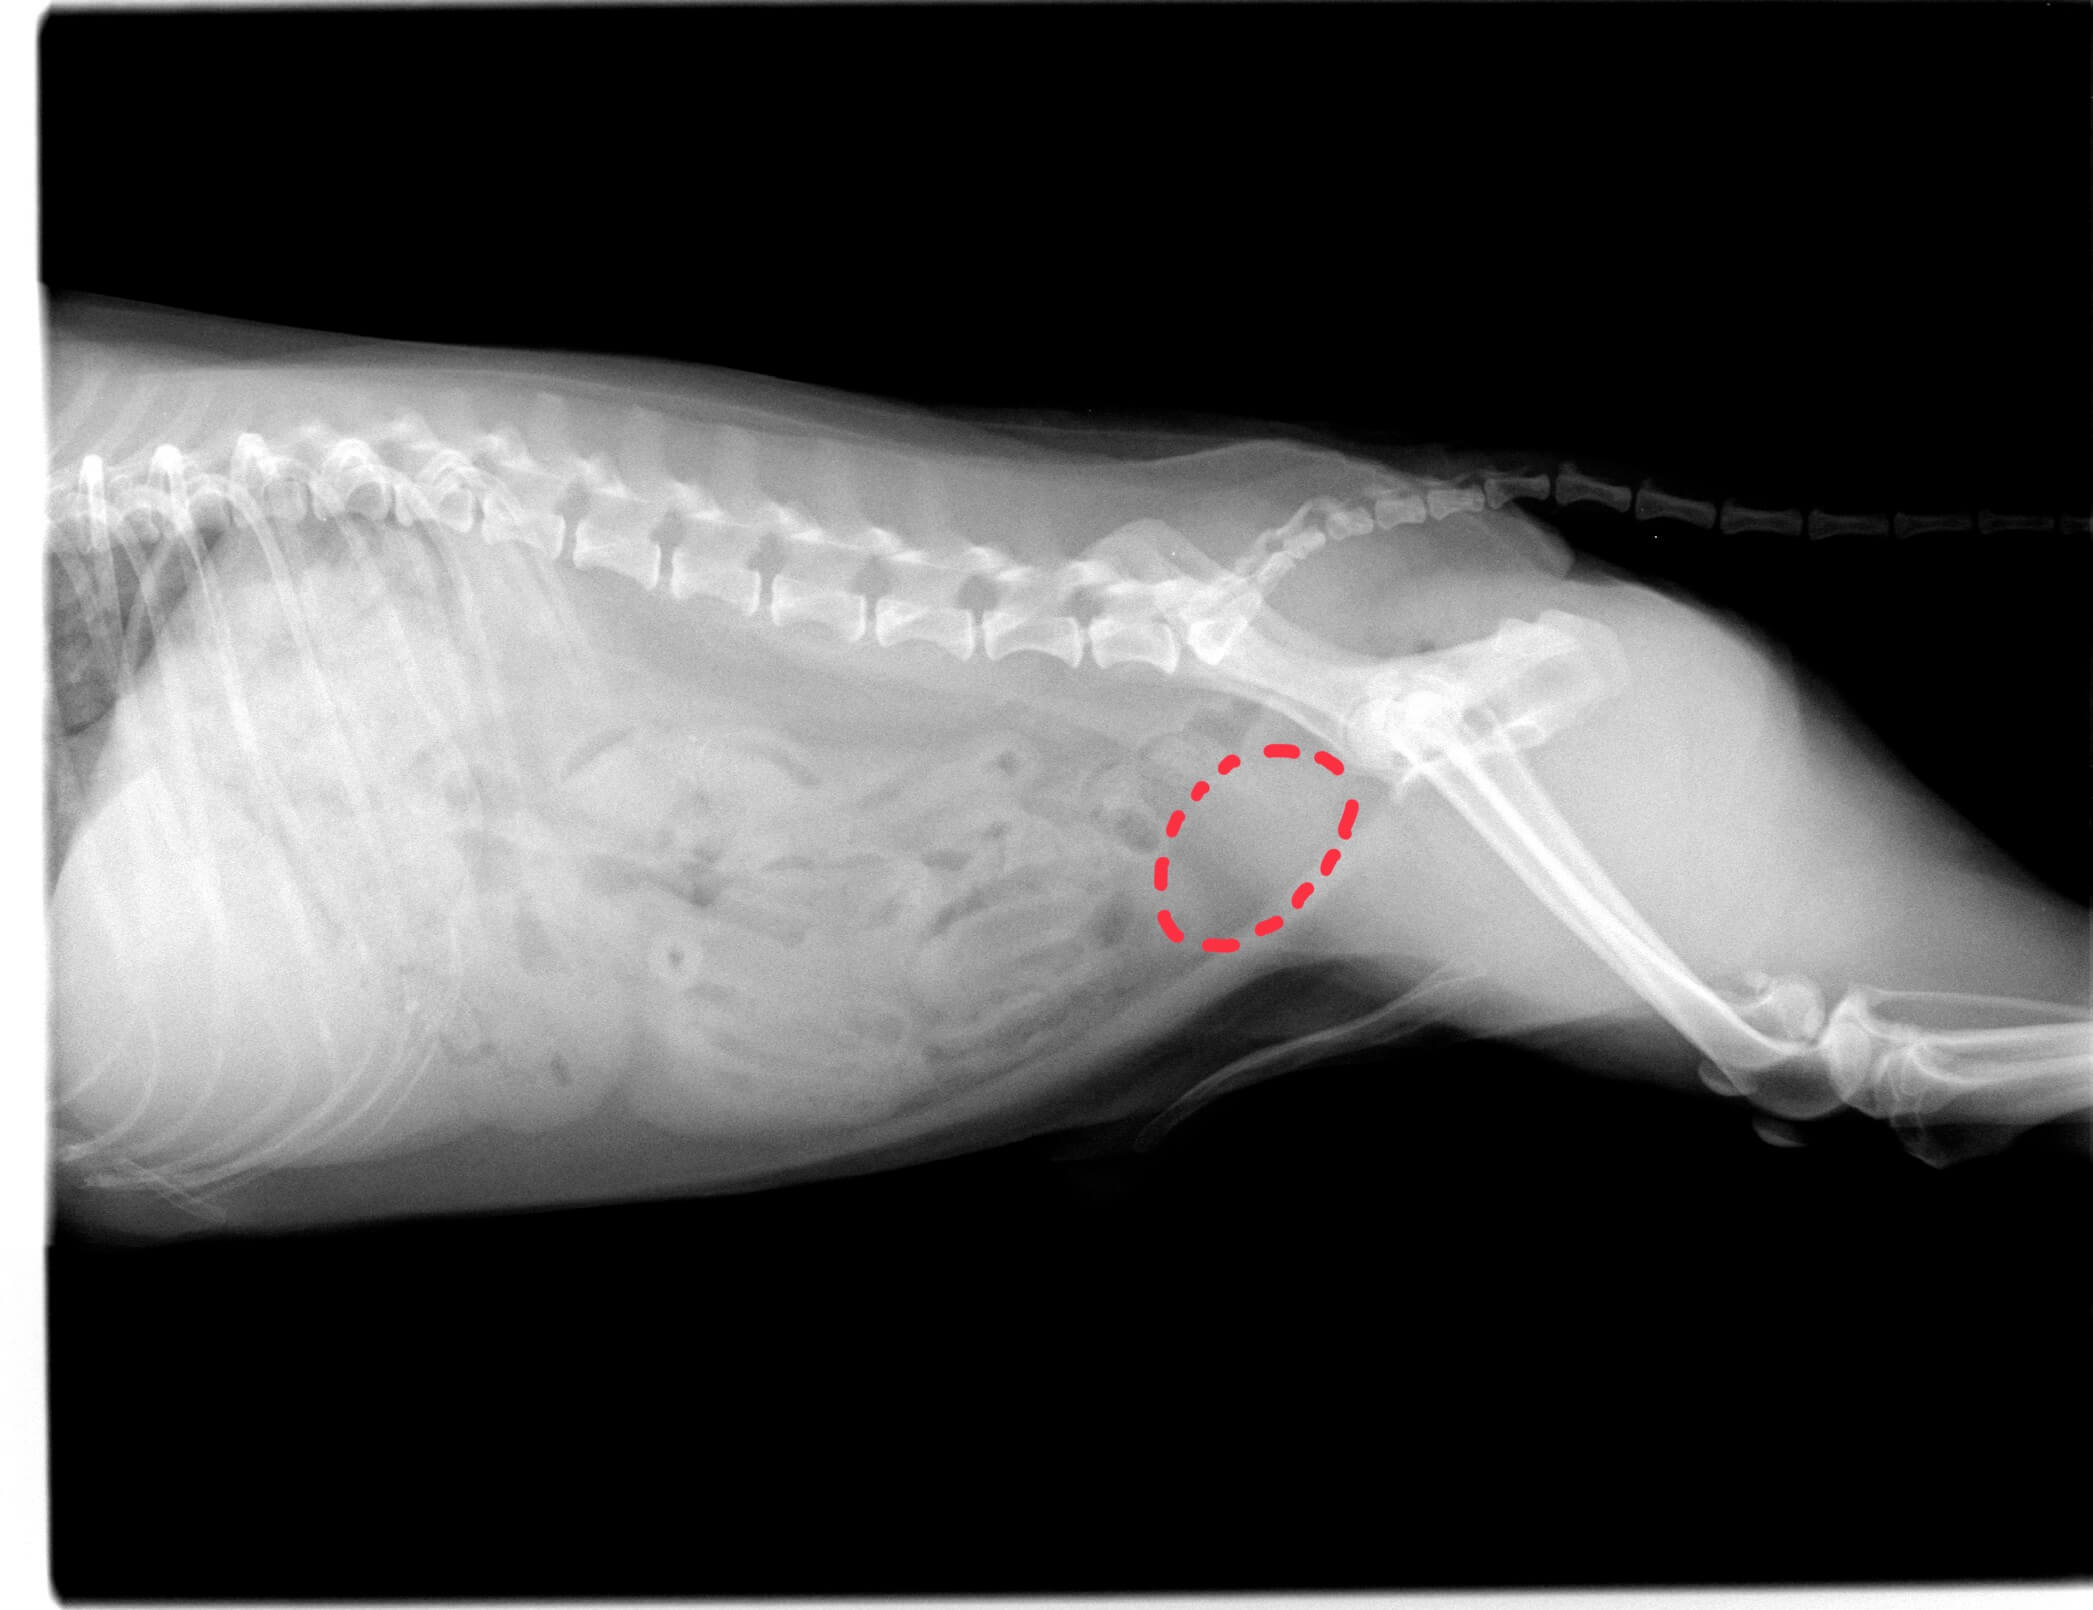

手術後のレントゲン画像です。

膀胱内の結石が取り除かれています。